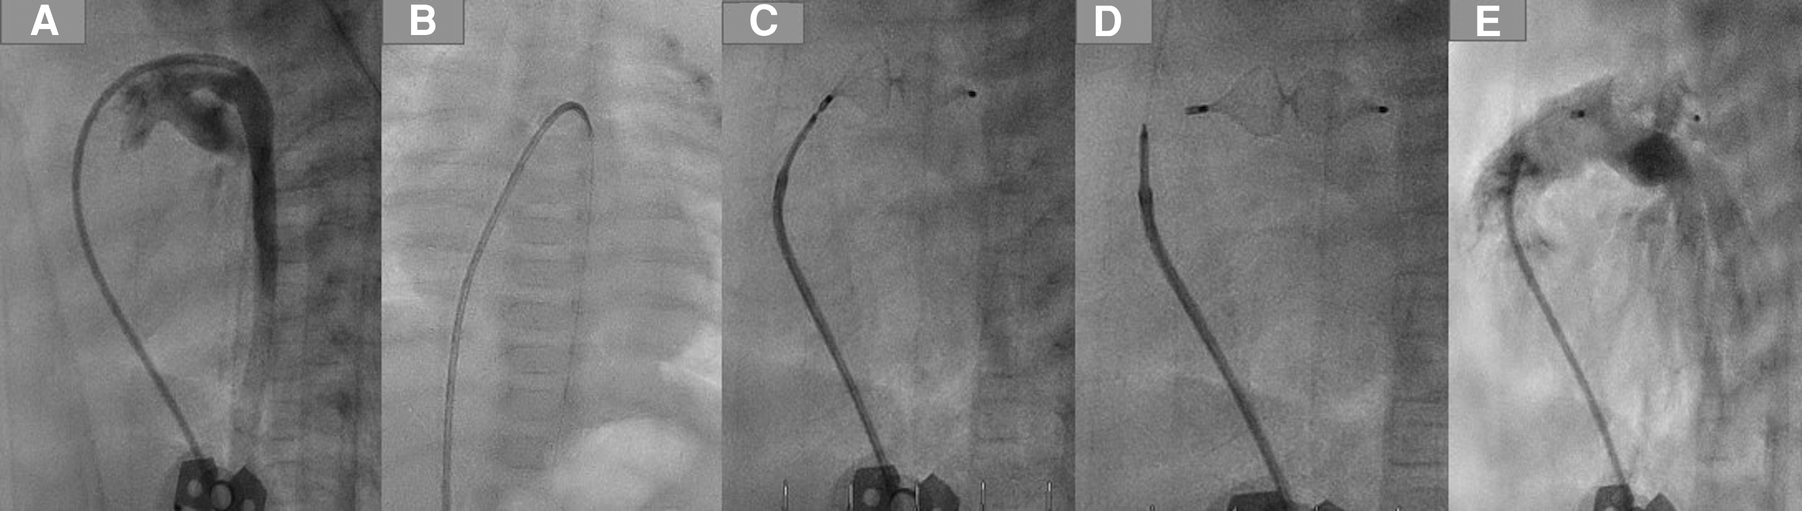

After deploying the device, we performed echocardiography to ensure the device's position and exclude a residual shunt and any device-related pulmonary stenosis or aortic stenosis. After verifying the device's position and the intervention's results, the delivery cable was detached from the device by rotating it anticlockwise using the plastic vice until it was wholly separated from the plug. The cable with the catheter and the short sheath were removed (Figure 2).

Figure 2

PDA closure with AP4 step by step. (A) Demonstrating the duct using a 4 F JR, which crossed the duct and was positioned in the descending aorta. (B) A 0.14 coronary wire was positionedin the DAO. (C) Plug 8/13.5 was employed in the duct. (D) Removing the delivery wire from the plug. (E) Angiography after the intervention, no residual shunt.